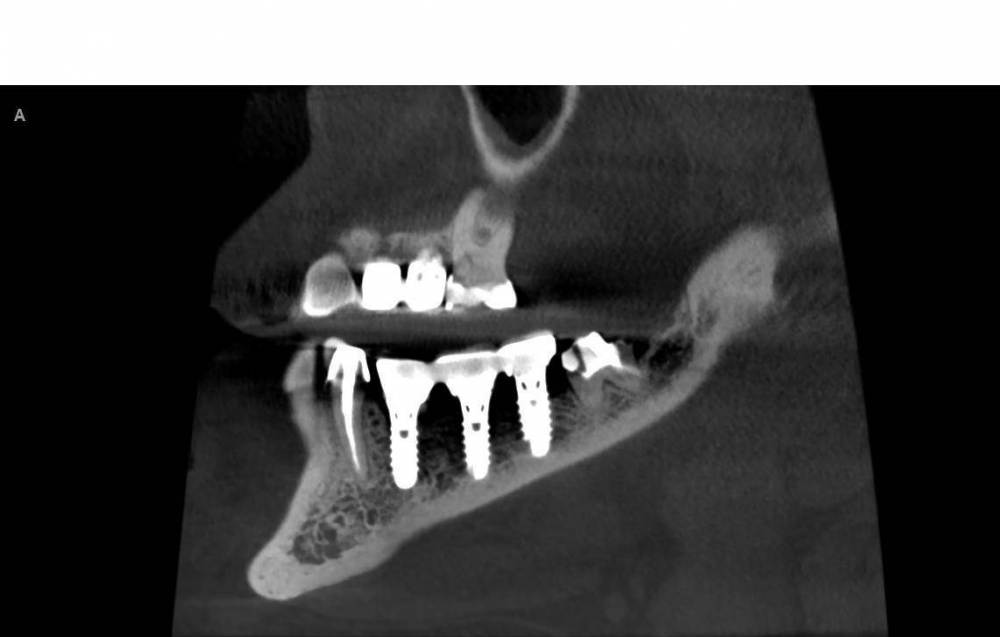

Turalyon Опубликовано 24 декабря, 2021 Поделиться Опубликовано 24 декабря, 2021 Приветствую, коллеги. У пациентки лет 10 назад установлены предположительно импланты Straumann, планируется замена коронок. Под старой коронкой вот такой мультиюнит, не знаю чем открутить. В каталоге подходящих ключей не нашел. 1) каким ключом можно попробовать открутить? диаметр около 3 мм 2)Что, если не откручивая снять оттиск с уже установленных мультиюнитов для изготовления новых коронок? Ссылка на комментарий

kramer Опубликовано 24 декабря, 2021 Поделиться Опубликовано 24 декабря, 2021 Это не мультиюнит, а монолитный абатмент. Откручивается специальным ключом. Или снимать оттиск с уровня абатмента 1 Ссылка на комментарий